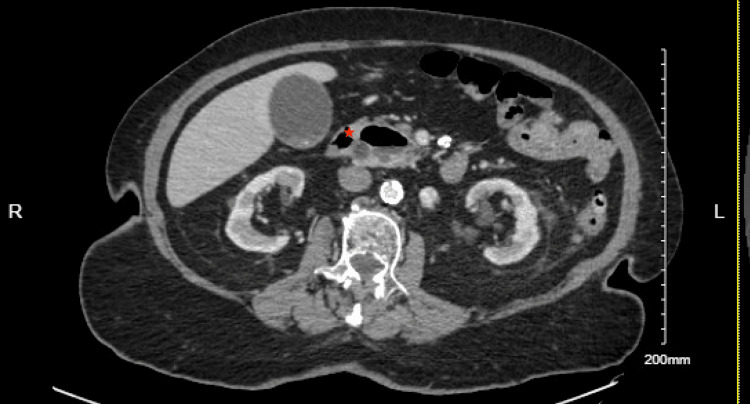

Upon arrival, the patient’s vital signs were stable, with a blood pressure of 161/68 mmHg, a heart rate of 78 beats per minute, a respiratory rate of 18 breaths per minute, and normal oxygen saturation on room air. She was afebrile, and her physical examination was largely unremarkable, with no abdominal tenderness noted. Labs were significant for elevated ALT 175 U/L and AST 134 U/L on presentation; alkaline phosphatase (77 U/L) and total bilirubin (0.3 mg/dL) were within the normal limit. A CT scan of the chest, abdomen, and pelvis with intravenous contrast showed dilation of the biliary and pancreatic ducts, along with findings of choledocholithiasis and a possible obstructive lesion at the head of the pancreas. A large duodenal diverticulum was also observed, encasing the distal portion of the common bile duct and suggesting biliary obstruction (Figures 1, 2). Follow-up imaging with MRI and MRCP confirmed dilation of both intrahepatic and extrahepatic bile ducts, with several filling defects in the common bile duct, consistent with choledocholithiasis, as well as CBD dilation and the presence of a duodenal diverticulum.